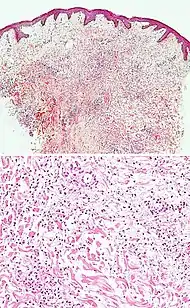

| Pigmented purpuric dermatosis |

|

|

|